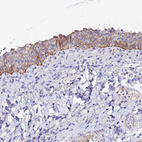

Anti-KRT17 Antibody

Polyclonal Antibody against HUMAN KRT17